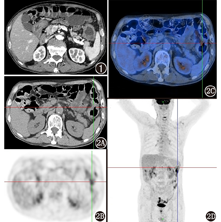

为明确病变性质,2015年9月1日于本科行18F-脱氧葡萄糖(fluorodeoxyglucose, FDG) PET/CT(德国Siemens Biograph 64排)显像,患者按体质量注射18F-FDG(上海原子科兴药业有限公司提供) 3.7 MBq/kg。PET/CT显像(图2)示:升结肠、降结肠、乙状结肠、直肠上段见局部肠壁增厚,FDG代谢轻度增高,最大标准摄取值(maximumstandardizeduptakevalue, SUVmax) 3.2~6.4;病灶周围局部脂肪间隙模糊,FDG代谢未见明显异常。诊断:直肠上段、结肠多节段肠壁增厚伴FDG代谢轻度增高,炎性肠病可能性大,请结合肠镜病理。

本例在影像学方面与炎性肠病较难鉴别。PET/CT图像表现为结直肠多处肠壁增厚,FDG代谢轻度增高,SUVmax为3.2~6.4。其中CT表现并不具有特异性,炎性肠病中亦有肠壁增厚、黏膜强化等CT表现。PET代谢特点方面,Groshar等[7]报道,活动期克罗恩病可见病变肠壁FDG代谢增高,病变肠道SUVmax为5.0±2.5,且代谢高低与炎性病变程度及活动程度相关;而溃疡性结肠炎亦有相似报道[8]。本例病灶SUVmax与上述文献报道的炎性肠病FDG代谢程度相似,CT表现亦无特异性,是误诊为炎性肠病的主要原因。Ciarallo等[9]也曾有类似报道。尽管PET/CT较难鉴别炎性肠病及EATL,但其在明确肠道病变范围方面具有明显优势[9]。